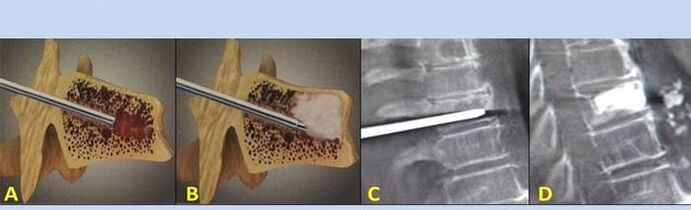

- Nukleoplastik – Entfernung des Bandscheibenkerns. Die Operation entlastet die Nervenenden.

- Vertebroplastie mit Punktion – Methode zur Stabilisierung der Wirbel. Während des Eingriffs füllt der Arzt die Hohlräume der Wirbelsäule mit Knochenzement.